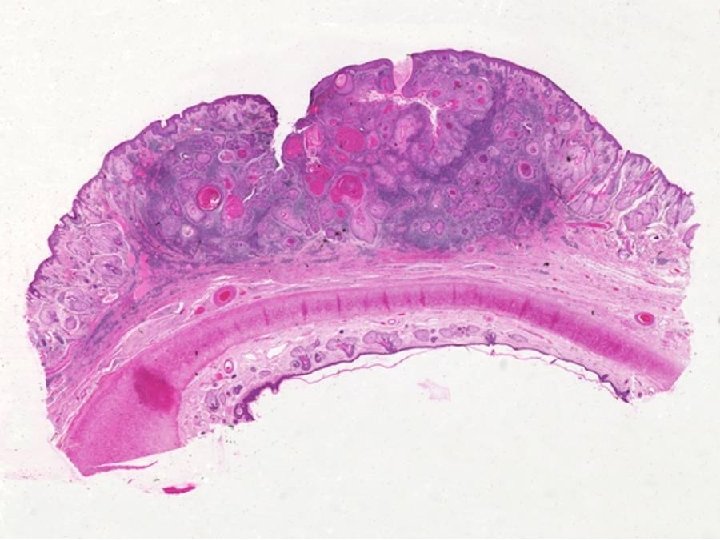

PREMALIGNANT/MALIGNANT • ACTINIC (Solar) KERATOSIS, i. e. precursor to SCC • SQUAMOUS CELL CARCINOMA, squamous “pearls”, intercellular bridges • BASAL CELL CARCINOMA, by far, MOST COMMON, BLUE palisading nests • MERKEL CELL CARCINOMA (TUMOR), VERY MALIGNANT AND LETHAL, LOOK LIKE SMALL CELL CA. OF LUNG

GENERAL COMMENTS • BOTH SCC and BCC related to SUN (i. e. , radiation) exposure. (as is MM also) • SCC also related to As, carcinogens, chaw, betel nut, HPV, familial, etc. • BOTH SCC and BCC can do local damage but very rarely metastasize or kill. • MERKEL CELL tumors metastasize early and extensively, like melanomas.